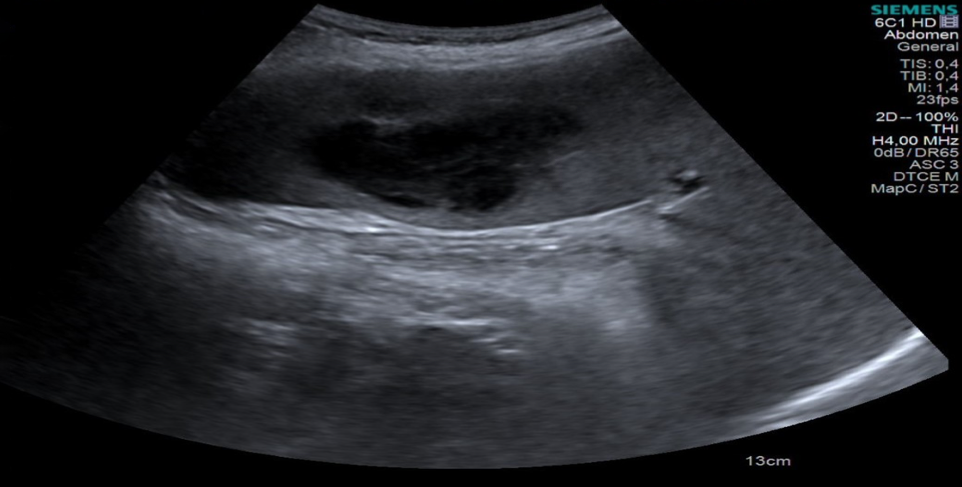

Abdominal ultrasonography identified a heterogeneous 60×45 mm abscess with a hypoechoic centre in an enlarged spleen and multiple small cystic lesions in the liver (Figure 1). Splenic abscess drained through a needle aspiration with temporary drainage catheter and several samples collected for microbiological examination; however, no sample was available for histopathological evaluation. Then, piperacillin-tazobactam 4.5 g every 6 hours was given empirically.